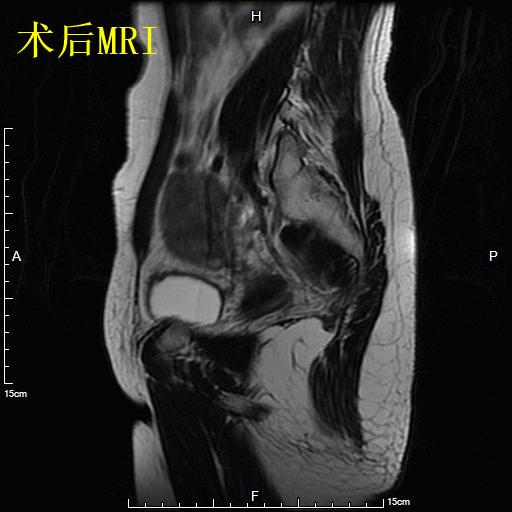

- 对比术后6个月复查MRI显示肌瘤已明显缩小,月经量已回复正常,生活质量明显改善。

术后6个月复查子宫MRI